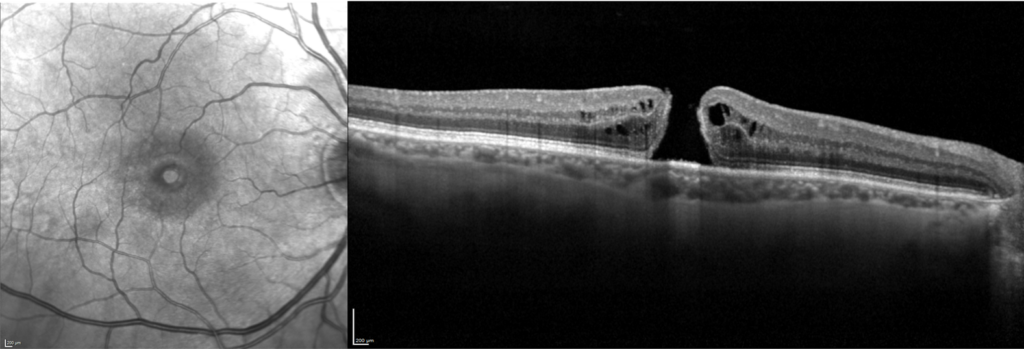

Trou maculaire en infrarouge et coupe OCT

Un trou maculaire est une atteinte de la rétine centrale (la macula), formant une interruption du tissu rétinien.

Il s’agit d’une complication du décollement postérieur du vitré.

Ce décollement vitréen est physiologique, mais il arrive qu’en se détachant, le vitré arrache une petite partie de la macula, formant ainsi un trou maculaire.